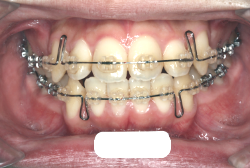

診断の結果、典型的なアングル2級1類の上顎前突です。上下歯列の正中の不一致も見られます。しかし、歯の大きさは平均値に近く、配列の凸凹がそれほど見られません。このまま放置すると、将来的には抜歯を伴う矯正治療を行う可能性が高くなりますが、このタイミングで適切な治療をすると、非抜歯治療が可能かもしれません。

矯正歯科医が着目するのは、奥歯の噛み合わせの位置関係です。前歯の位置にそれなりの差が生じていても、奥歯の位置が正しければそれほど重症という評価にはなりません。このケースの場合は、上下の第一大臼歯の位置関係は、直線的に一致しているタイプでした(矢印が一致)。混合歯列時期の奥歯の位置関係としては、ほぼ正常な状態といえますが、症状から言うと、上の奥歯をもっと後ろに下げてやることができれば、上顎歯列全体に余裕ができるので、凸凹も解消できるし、前歯の傾きを内向きに修正することもできると考えられました。しかしこのまま全体に永久歯が生えきってしまうと、上の前歯が出たままになってしまいますので、生え替わりが完了する前に大急ぎで奥歯を後ろに下げる必要があると判断しました。

こういう症状でもっとも効果があるのが、顎外固定装置と言って、お口の外部から奥歯に力をかける方法です。 写真の装置はネックバンドというタイプの装置です。この装置は取り外し式ですので、夜寝るときに毎日自分で取り付けて、寝ている間に少しずつ上の奥歯を後ろに下げていきます。この装置には、奥歯を後ろに下げる効果だけでなく、上顎の過剰な成長発育の抑制、下顎の成長促進作用があるとされており、上顎前突の症状にはいずれも有利な効果が期待できます。

ネックバンドを1年半使用して、上顎大臼歯が十分後ろに下がったところで、裏側にリンガルアーチという固定のワイヤーを取り付けて、新しく生じた隙間が狭くならないよう「保隙(ほげき)」という処置をして、永久歯が生えそろうまで待機中の様子です。配列全体に隙間が生じているのがお分かりいただけると思います。これだけの隙間が確保できていれば、抜歯をしなくても、あとで上の前歯を内側に理想的な角度で引っ込めることができます。このように完全に永久歯列になる前に、十分な隙間が確保できるかどうかが、非抜歯で矯正できるかどうかの分かれ目になります。

初診時と違い、上の奥歯がより後方に下がっていることが分かります。ただしこの段階では奥歯は後ろに下がりすぎの状態です。しかし次の段階でマルチブラケット法を始めると、上の奥歯は次第に前にズレて来ます。最終段階で正しい位置にするためには、この段階では余分に後ろに下がっている必要があります。

第2段階としてマルチブラケット法を非抜歯で1年間行いました。歯の傾斜が修正され、正中も一致し、美しく機能的な配列に仕上がりました。再診時に確保した隙間をすべて使って、すべての永久歯を理想的な位置に配列することができました。前傾していた上の前歯は真っ直ぐに直立し、完全な正常咬合が確立できています。